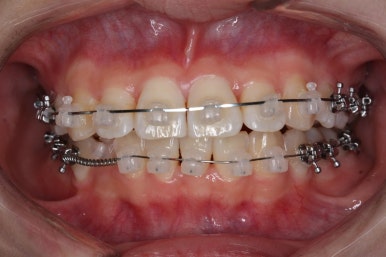

우선 윗니부터 가지런하게 합니다. 그리고 아랫니는 가지런하게 할 준비를 하죠.

화살표에 보이는 부착물의 이름이 바이트터보 입니다.

깊게 맞물리는 앞니, 즉 과개교합을 개선하기 위해 일시적으로 이용하는 장치입니다.

굉장히 효율적으로 과개교합을 개선할 수 있습니다.

아랫니에도 이제 장치를 붙였습니다.

과개교합인 채로 아랫니에도 장치를 붙이게 되면 아랫니 장치가 깨물려서 다 떨어지거나 부서지기 쉽습니다. 따라서 바이트터보는 굉장한 역할을 하게 됩니다.

눈으로 보기에는 과개교합이 개선이 된 것처럼 보이지만 아직은 아닙니다. 바이트터보가 남아있는 채로도 어금니가 맞물려야 진짜로 개선된 것이죠.